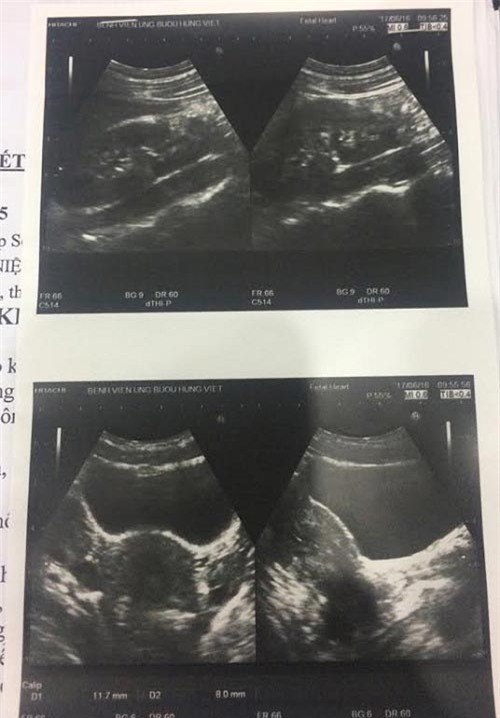

Kết luận của bác sĩ sau khi tiến hành siêu âm chụp chiếu, phát hiện bệnh nhân Hiền có dị tật.

Hình ảnh siêu âm ổ bụng của bệnh nhân Hiền sau khi được phẫu thuật.